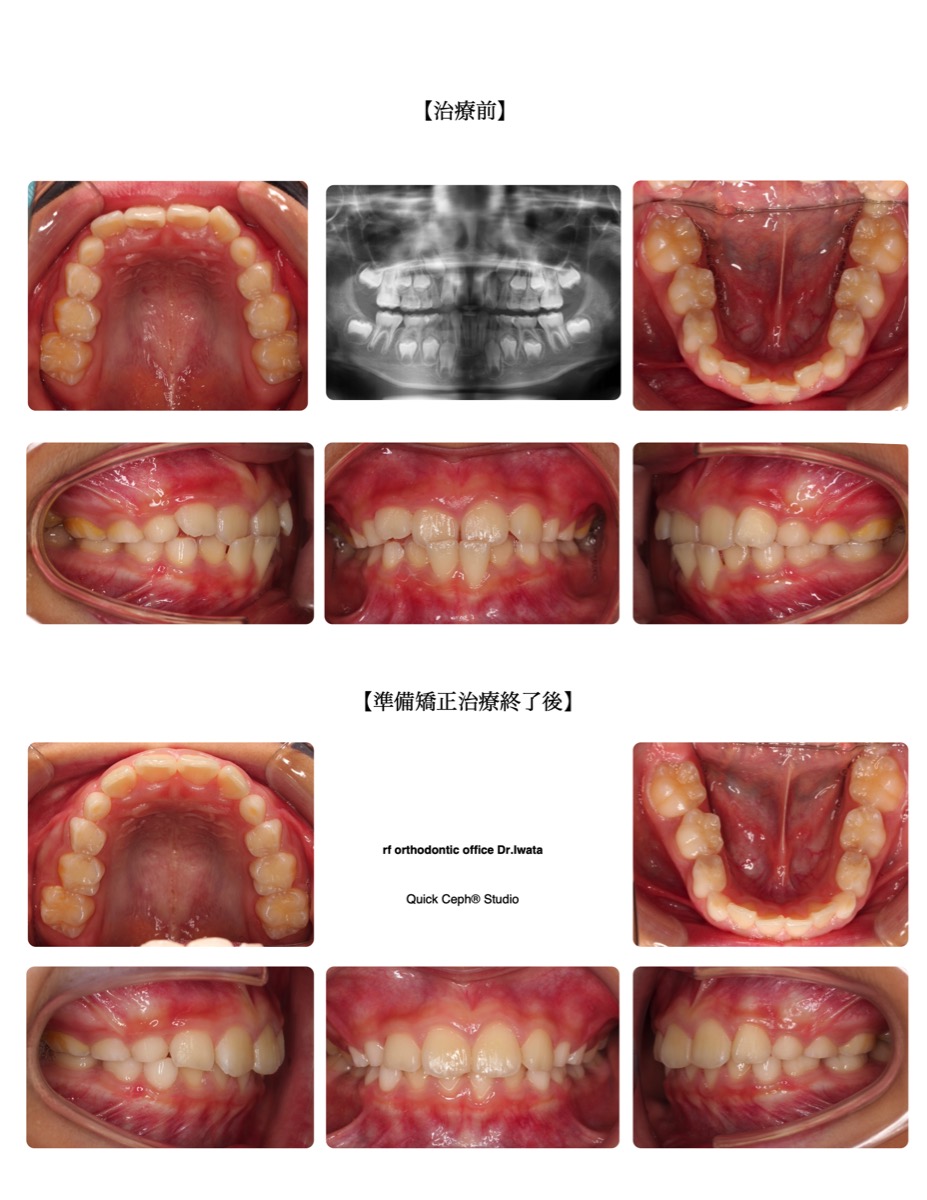

【主訴】前歯が受け口になっている。前歯がガタガタしている。

【主な症状】反対咬合 叢生

| 治療期間・回数 | 10ヶ月・7回 |

| 性別 | 男性 |

| 年齢 | 7歳 |